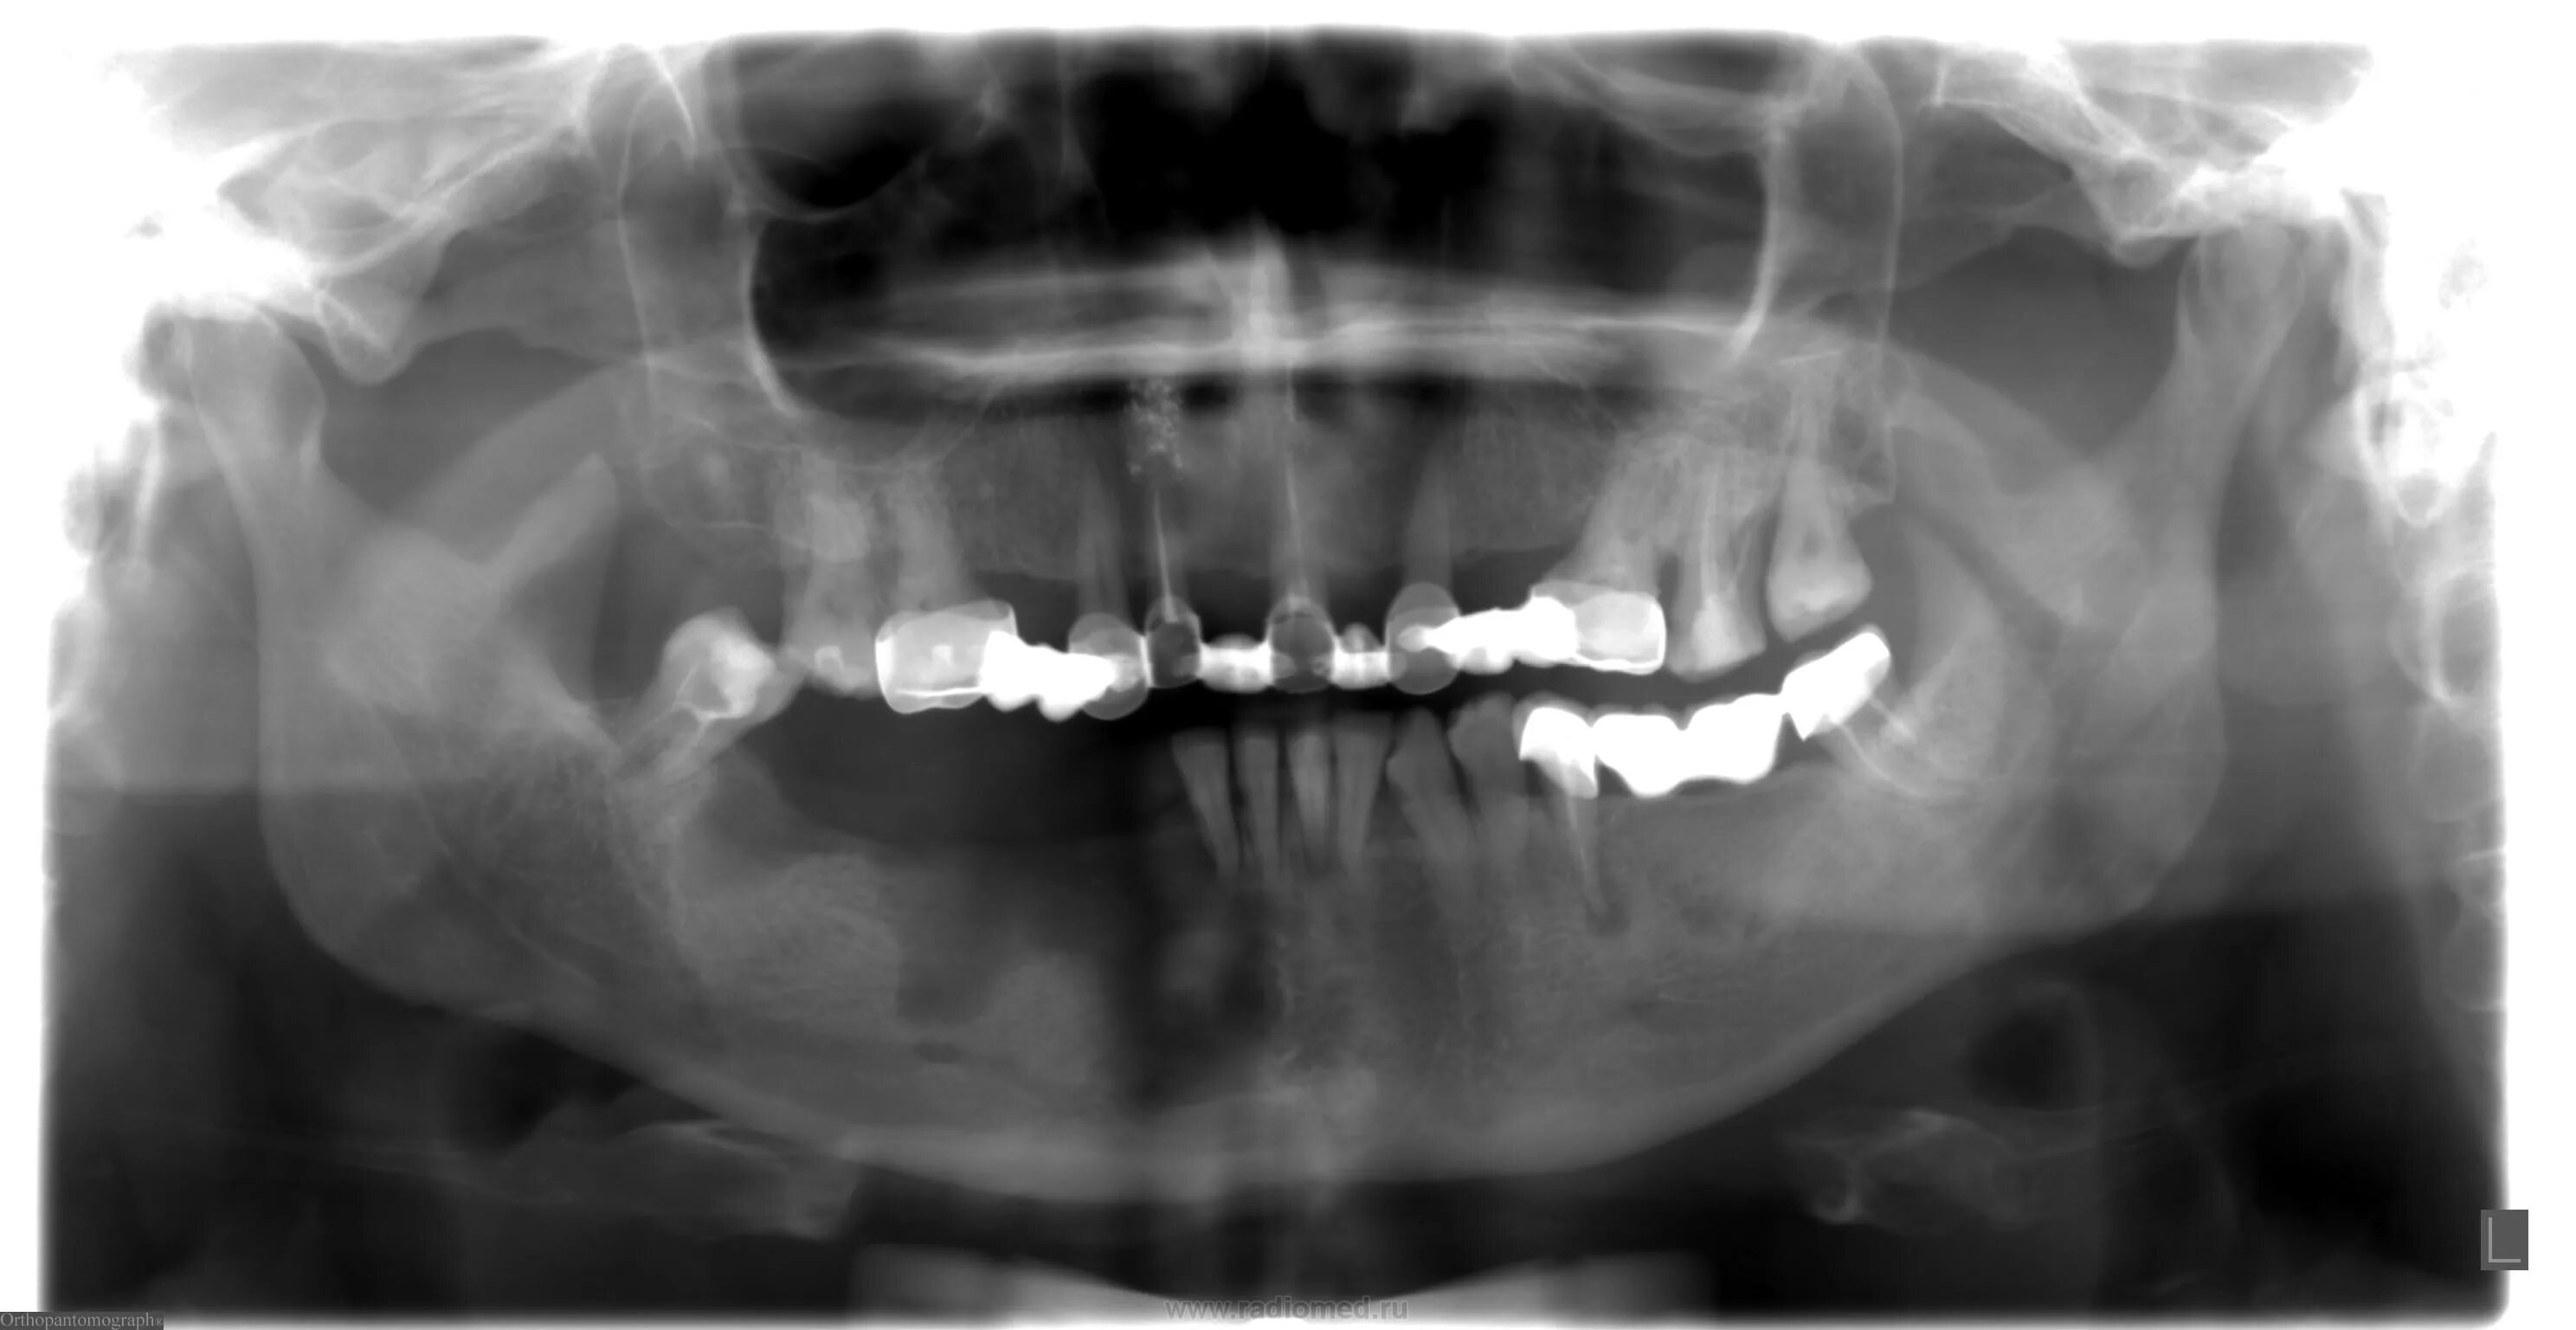

Подострая одонтогенного остеомиелита.. одонтогенный остеомиелит рентген. остеомиелит челюсти рентген. одонтогенный остеомиелит челюсти рентген.

Одонтогенный остеомиелит рентген. хронический остеомиелит челюсти. клиника острого остеомиелита нижней челюсти. муфтообразный инфильтрат.